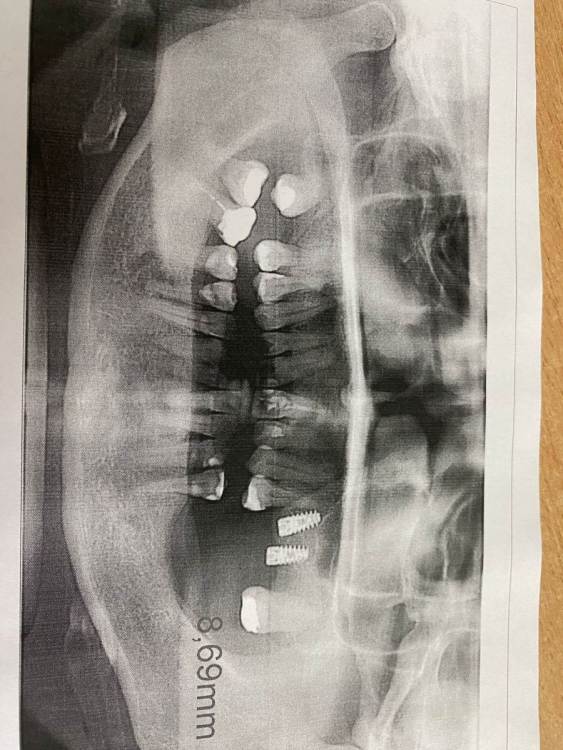

Жандос Муратович Опубликовано 11 августа, 2023 Поделиться Опубликовано 11 августа, 2023 Имплантация 2-х имплантов в обл 25,26 зубов 05.05.2023 прошло 3 месяца что порекомендуете? 1 Ссылка на комментарий

Жандос Муратович Опубликовано 12 августа, 2023 Автор Поделиться Опубликовано 12 августа, 2023 Переставлять 26 или попробовать закрыть? положительного опыта в наращивание нет, по этому спрашиваю) И еще какие отзывы будут о препарате? Если можно админы перенесите в закрытый раздел Ссылка на комментарий

TIGER Опубликовано 13 августа, 2023 Поделиться Опубликовано 13 августа, 2023 @Жандос Муратович удалять Ссылка на комментарий

Большой Зеленый Опубликовано 15 августа, 2023 Поделиться Опубликовано 15 августа, 2023 6 надо переставлять Ссылка на комментарий